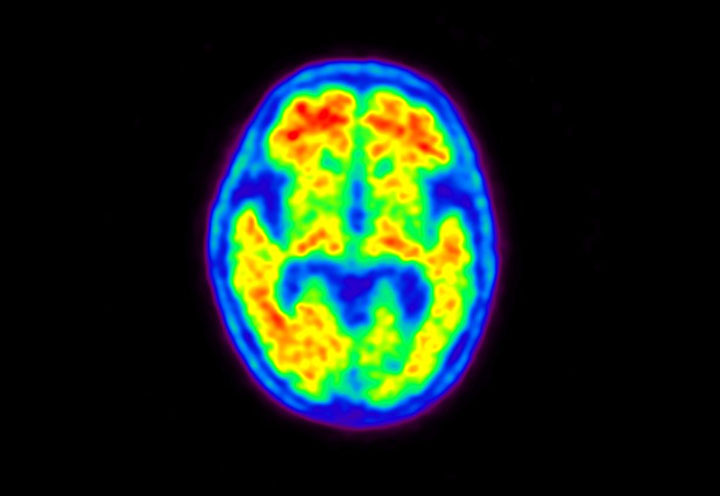

Head / Case5 : Amyloid

Axial

Courtesy : Kindai University Hospital

- Imaging protocol

- Injected dose: 4.27 MBq/kg, 18F-Flutemetamol

- Uptake time: 99 minutes

- Scan time: 20 minutes